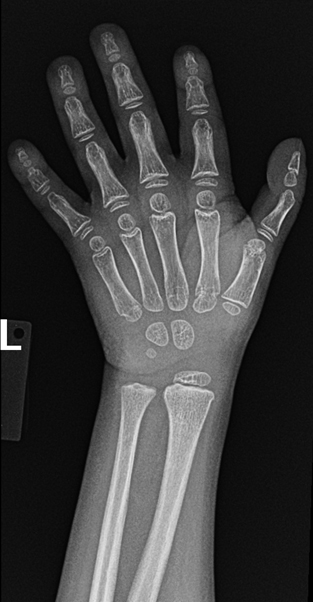

An interesting finding in fanconi anemia is a triphalngeal thumb Al Salam H, Lustosa L, Ranchod A, et al. Triphalangeal thumb. Reference article, Radiopaedia.org (Accessed on 15 Aug 2025) doi.org/10.53347/rID-1…

An interesting finding in fanconi anemia is a triphalngeal thumb

Al Salam H, Lustosa L, Ranchod A, et al. Triphalangeal thumb. Reference article, Radiopaedia.org (Accessed on 15 Aug 2025) doi.org/10.53347/rID-1…